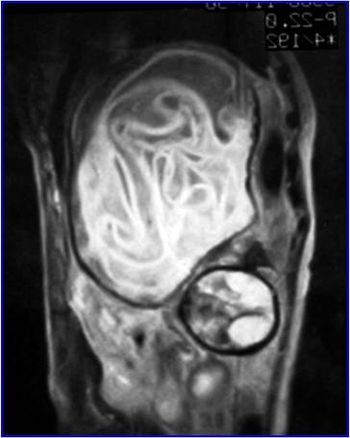

Can you diagnose this mostly asymptomatic patient but with weight loss and abdominal discomfort?